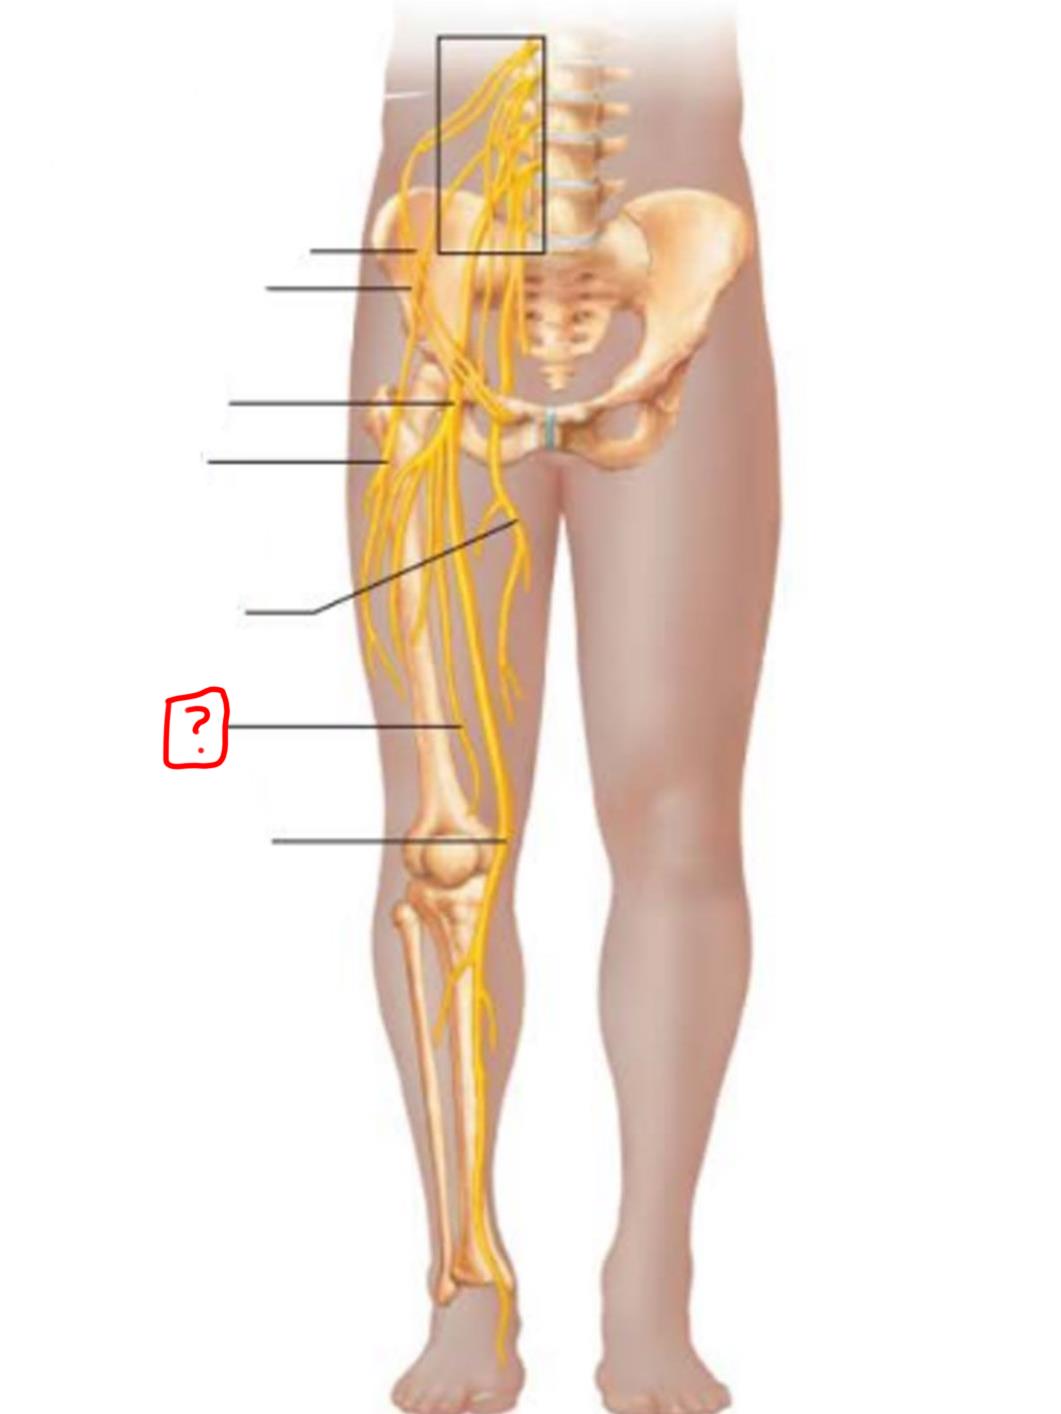

iliohypogastric

ilioinguinal

genitofemoral

lateral femoral cutaneous

obturator

femoral

femoral

lateral femoral cutaneous

obturator

anterior femoral cutaneous

saphenous